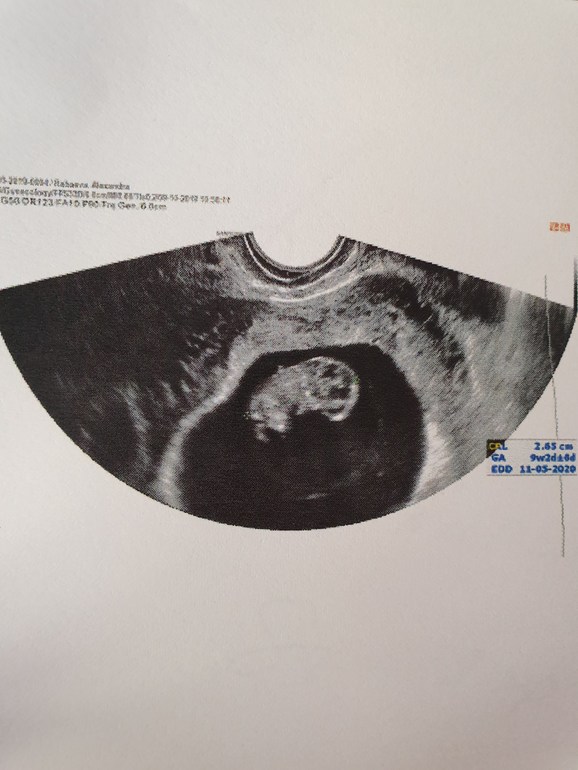

9+6 по М , 9+2 по УЗИ !

УЗИ, КТГ, доплерНу вот мы подросли на пару деньков и догоняем сроки по М ( хотя в заключении написано 9+5 и 8+5🤔 , но это не важно) главное, что с малышастиком все хорошо😍. А вот, к стати и он 🤩